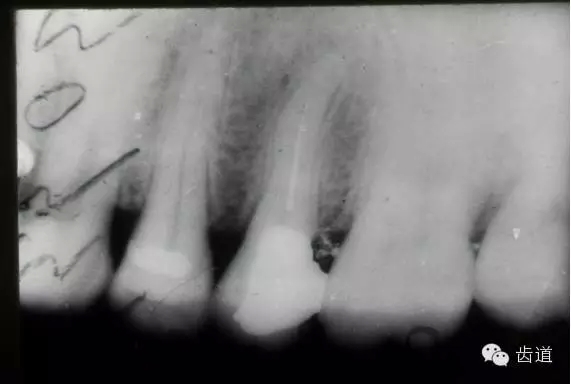

左上5牙頸部側(cè)穿

開髓時鉆針進(jìn)入方向與根管走行方向不一致,鉆針需改變方向時。

牙長軸傾斜,在傾斜方向的髓腔壁易穿孔